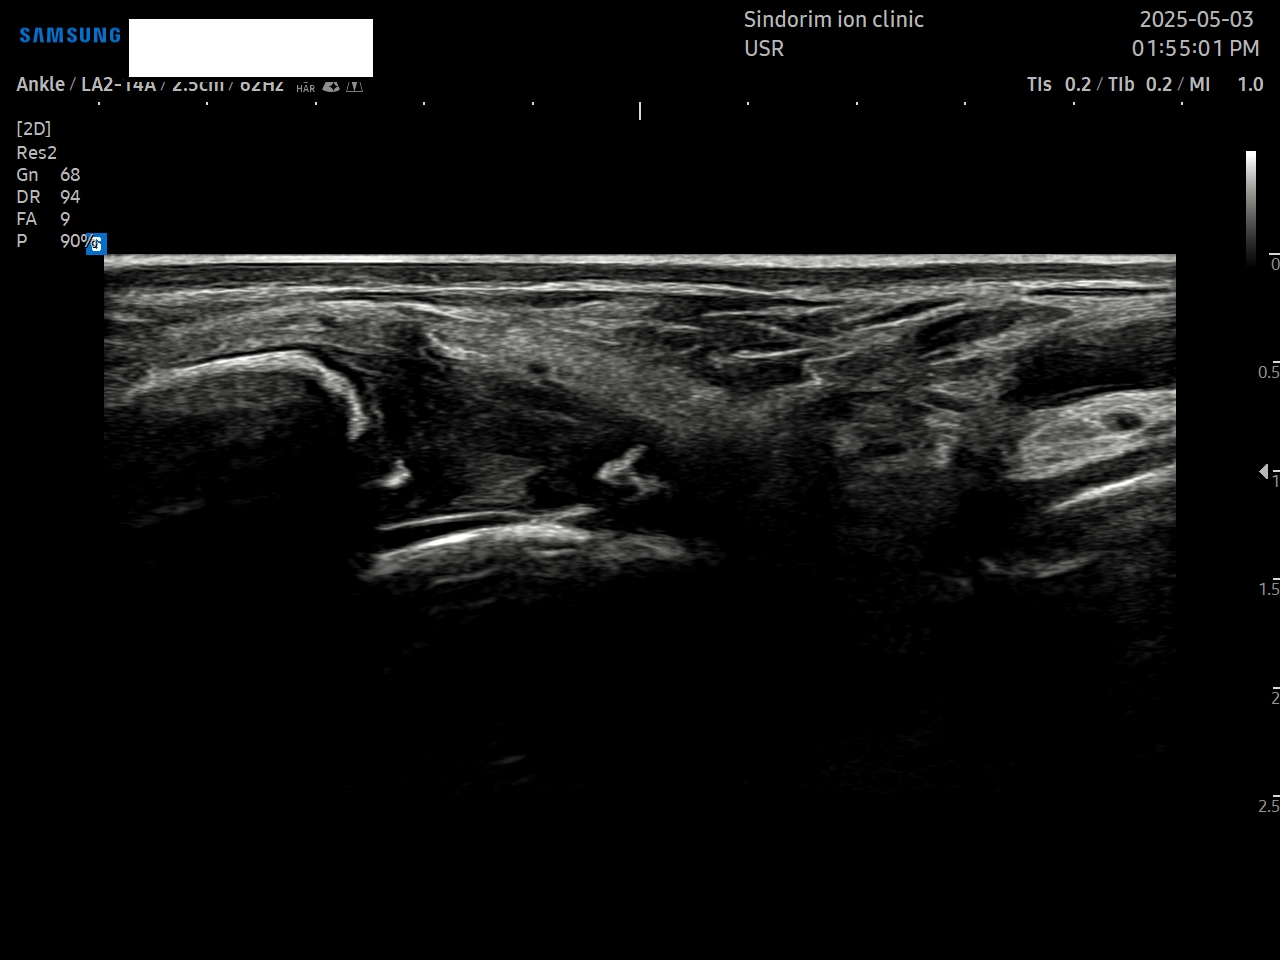

- 치료기간 : 25 . 5 . 3 ~ 25 . 9 . 11

- 치료횟수 : 10 회 (2 cycle)

우측 발 (치료 전 → 후)